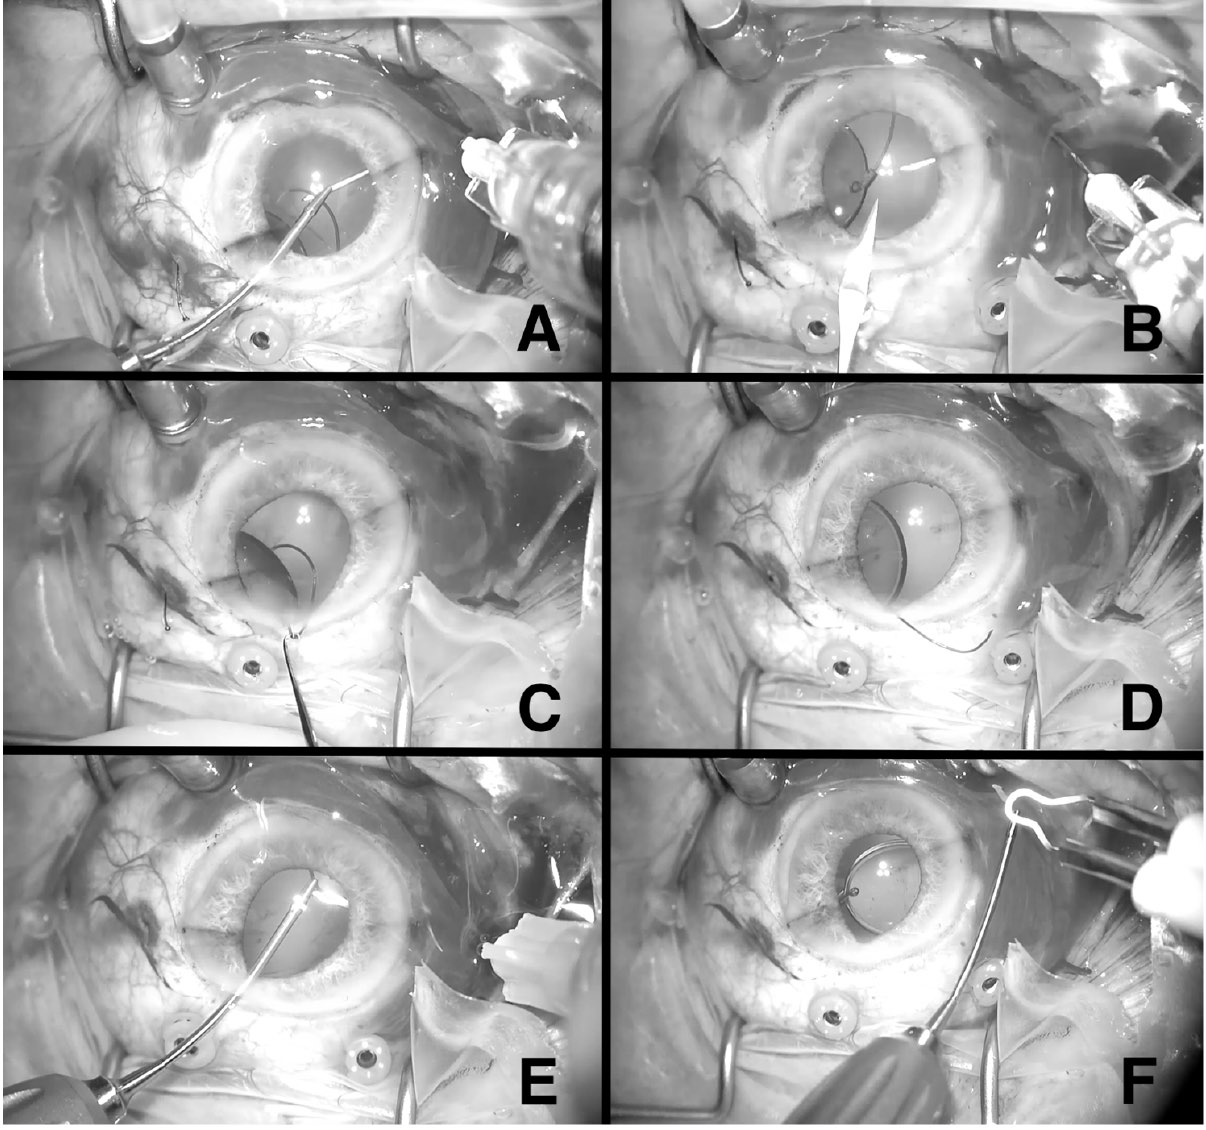

In each case, a standard 3-port 23-gauge or 25-gauge PPV was concurrently performed with IOL rescue and needle-assisted ISHF. Figure 1 shows key portions of the procedure. After a complete vitrectomy was performed and an intracameral viscoelastic was injected, the PMMA IOL was elevated into the anterior

chamber with an intraocular forceps. Paracenteses were made at the superotemporal and superonasal limbus, and a

3 mm lamellar clear corneal incision (CCI) was created at the superior limbus with a keratome blade. If associated capsule, Soemmerring ring, or both were adherent to the IOL, they were removed through the superior corneal wound with the assistance of an intraocular forceps and scissors.

After a toric marker was used to delineate the horizontal meridian of the cornea centered on the central visual axis, scleral markings were made 3 mm posterior to the limbus 180 degrees apart. The trailing haptic of the IOL was then externalized from the eye via the superior corneal wound. Next, 2 thinwalled 30-gauge needles (TSK Lab) were introduced into the vitreous cavity via opposing beveled sclerotomies initiated at the scleral markings. Using an intraocular forceps and hypodermic needles as originally described by Yamane et al,9 the leading and trailing haptics were docked into the 2 needles, first externalizing the leading haptic and then the trailing haptic. The

creation of the superior lamellar corneal incision allows for a more ergonomic angle to dock the trailing haptic into the second needle. Using thermal cautery, terminal bulbs were formed at the end of each externalized haptic and the haptics were placed into the subconjunctival space to secure them within their respective sclerotomies.